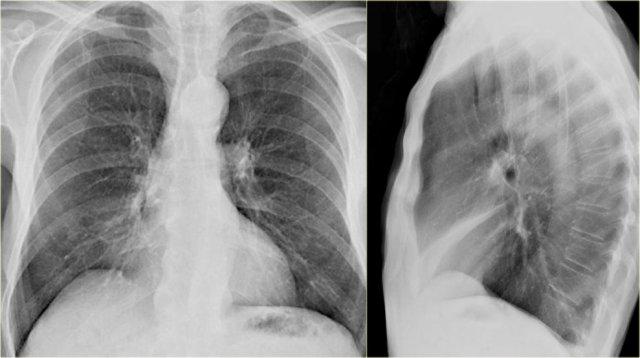

Xẹp thùy giữa phổi phải

Hãy quan sát kỹ các hình X-quang trước, sau đó tiếp tục đọc.

Các dấu hiệu là gì?

- Xóa mờ bờ tim phải (dấu hiệu bóng mờ)

- Đám mờ hình tam giác trên phim nghiêng do xẹp thùy giữa

Thông thường, xẹp thùy giữa phổi phải không gây nâng cao cơ hoành phải đáng kể.

Ngực lõm (pectus excavatum) có thể bắt chước hình ảnh xẹp thùy giữa trên phim thẳng, nhưng phim nghiêng sẽ giúp phân biệt được vấn đề này.